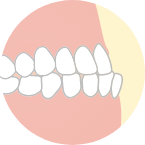

下の歯が出ている

(いわゆる出っ歯)